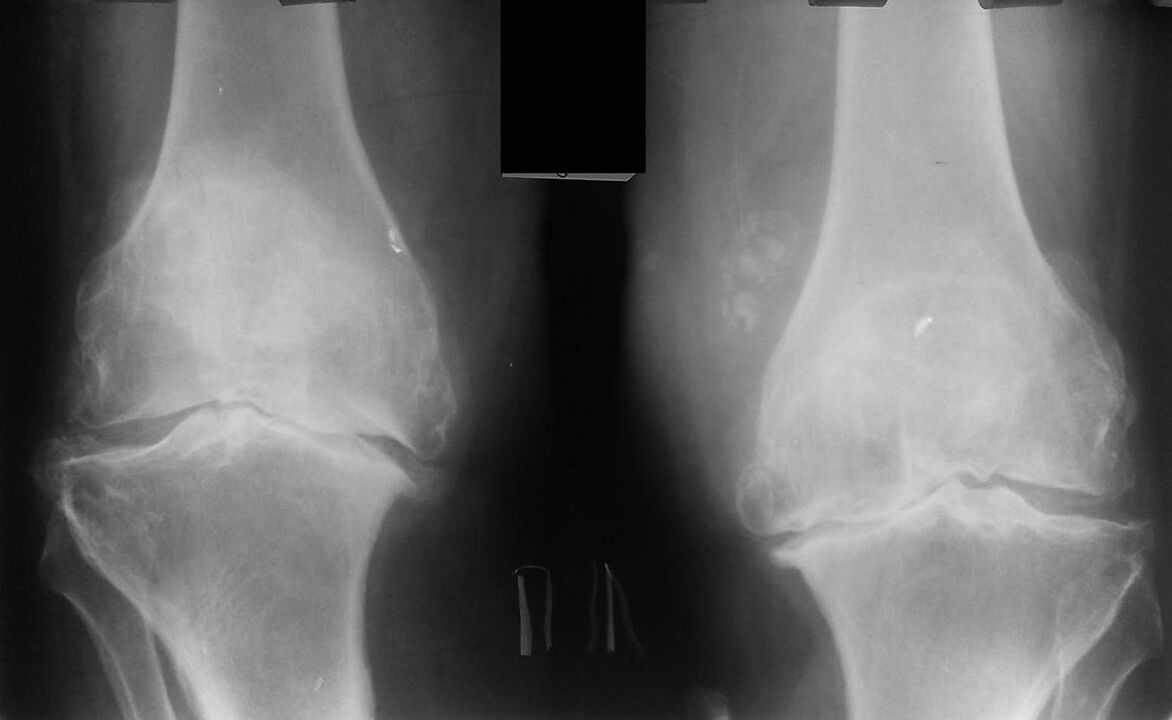

This diagnosis is made on the basis of patient complaints, examination data, palpation of the diseased joint and X-ray examination.

X-ray is a standard research method that allows you to confirm the diagnosis, establish the degree of pathological changes, monitor the dynamics of the process, and also allows you to exclude other pathological processes (for example, tumors)in the tibia and femur. .

It should be noted that the main changes in the structures of the knee joint on x-rays may be absent. Subsequently, the narrowing of the joint space and the compaction of the subchondral zone are determined. The articular ends of the femur and especially the tibia expand, the edges of the condyles become sharp.

- The second stage is characterized by more acute pain, which does not stop with the immobility of the limb. A crackle appears. Fluid accumulates in the joint cavity, the x-ray shows the deformation and growth of the bone. The patient at this stage tries in every possible way not to move the affected limb. The attending physician prescribes injections and chondroprotectors - drugs that help restore cartilage tissue.

- In the final third stage, the pain becomes constant and often worsens with changing weather conditions. The X-ray shows a significant deformation of the knee, which can only be corrected by surgery, the patient must take a complex of chondroprotectors. The patient's gait changes: he walks on half bent legs or rolls from side to side.